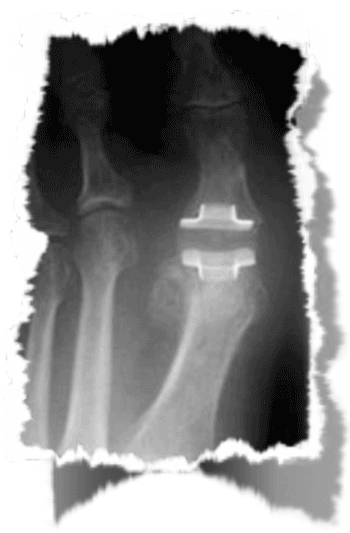

RADIOGRAPHIE

3 stades radiographiques

( cliniquement : hallux dolorosus)

( douleur et enraidissement articulaire)

2 - LES PROTHESES ARTICULAIRES

De nombreuses prothèses ont été développées mais les résultats sont encore à améliorer et les recherches sont encore à poursuivre.

La reprise d'un échec de prothèse, qui se descelle, nécessite le plus souvent la réalisation d'une arthrodèse dont la réalisation et l'efficacité est plus aléatoire qu'une arthrodèse réalisée d'emblée et qui reste l'intervention de référence.

Les prothèses en silicone sont abandonnées ; les prothèses à glissement en cours d'évaluation mais...